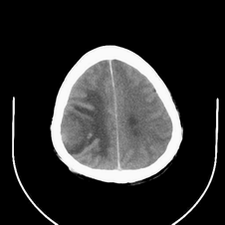

标题: CT25808:男,48岁,头痛多年,近段时间头痛加重伴步态不稳 [打印本页]

标题: CT25808:男,48岁,头痛多年,近段时间头痛加重伴步态不稳

平扫:右颞顶叶病灶呈等低密度伴大面积水肿,脑室受压变形。增强:病灶显著强化。考虑淋巴瘤或黑色素瘤。

1)不排除黑色素瘤可能;建议行mri检查。2)大脑镰下疝。3)脑积水(梗阻性)。